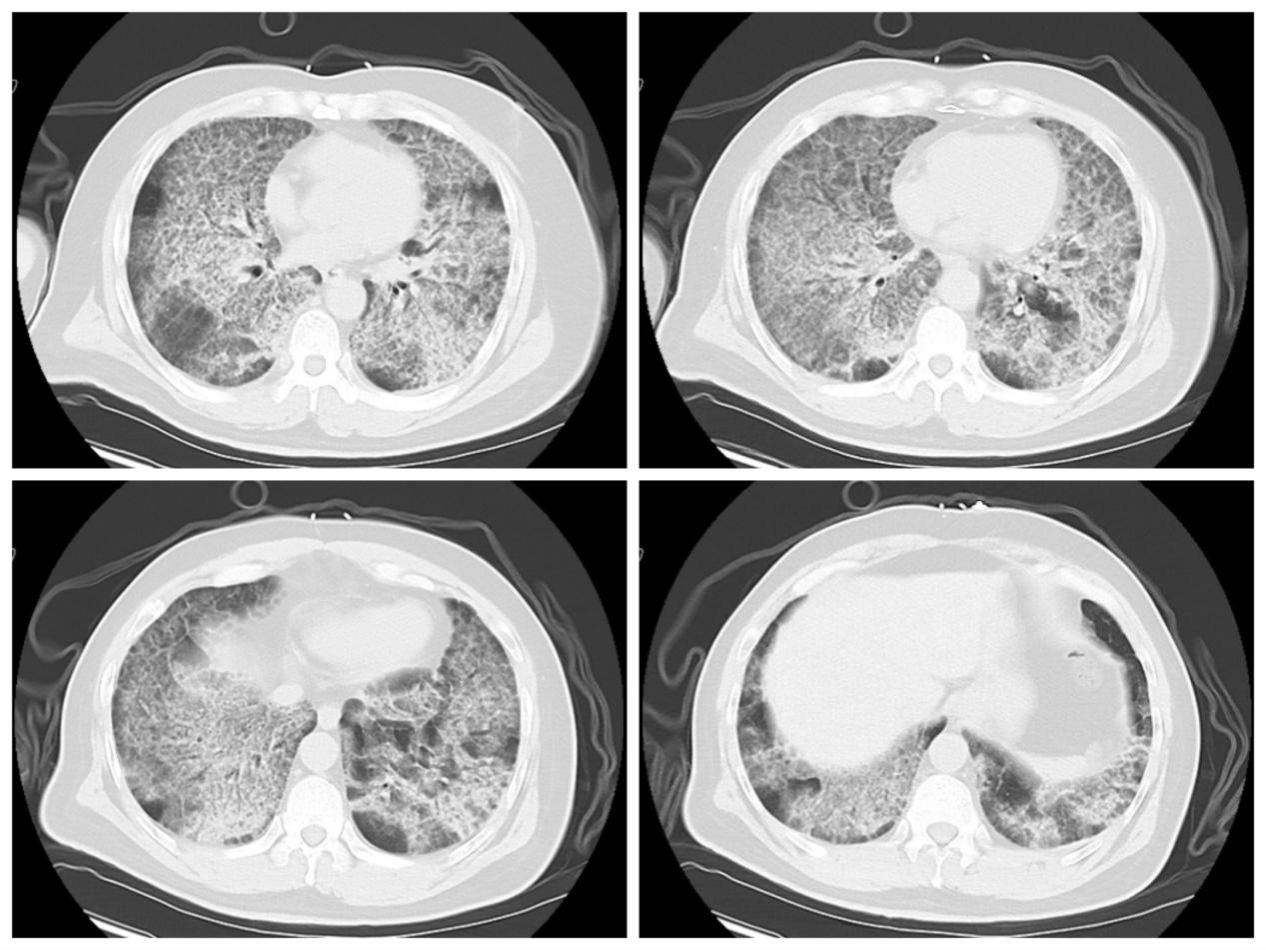

术后,患者在ECMO支持下转入呼吸与危重症医学科RICU继续治疗。在长达11天的ECMO支持期间,RICU医护团队日夜坚守,严密监测,精准调整抗感染、抗凝策略和ECMO、呼吸机支持参数。随着患者自身肺功能逐渐改善,复查血气指标显著好转,胸部CT显示双肺弥漫性阴影较入院时明显吸收。最终成功撤除ECMO,并顺利脱离呼吸机、拔除气管插管。出院时,患者在不吸氧的情况下,血氧饱和度维持在正常水平,活动能力恢复,实现了从“命悬一线”到“行动自如”的生命奇迹。

全肺灌洗前后影像资料对比